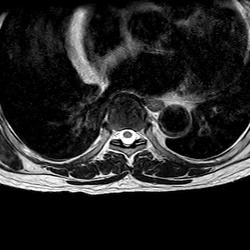

MRI_eAX_T2W_Thoracal_702

42 photos